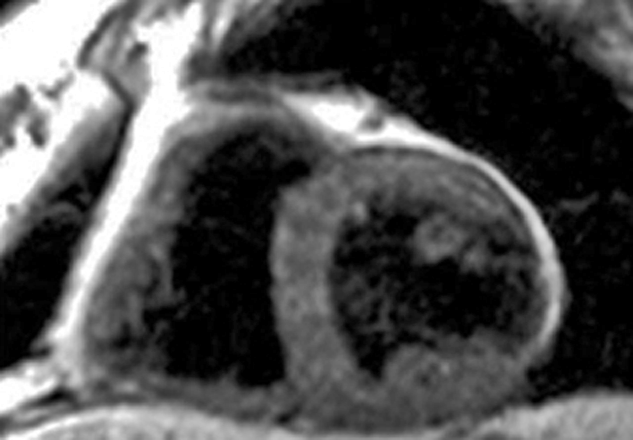

Manganese also has an affinity for the myocardium and could act as biomarker in heart disease. Manganese ions compete with calcium for entry into cardiac cells. There the ions bind to macromolecules and influence the relaxation of cell and tis­sue water. Heart diseases gradually inactivate calcium transport mechanisms due to lower metabolic activity. Thus, manganese uptake is reduced accordingly; man­ga­nese-induced changes of tissue relaxation reflect tissue calcium homeostasis and thus myocardial viability (Figures 13-17 and 13-18) [⇒ Skjold 2004, ⇒ Skjold 2007] and allows the assessment of stunned and viable myocardium [⇒ Spath 2021, ⇒ Singh 2023].

Figure 13-17:

Mn-DPDP: A short axis single shot IR Turbo-FLASH image of a heart before contrast agent application (top), and another image of the same heart with the same parameter settings one hour after the end of the contrast agent infusion (bottom).

To the right of each image sectoral divisions of the left ventricle are shown, depicting R1 color maps of the respective slice. The left ventricle shows a marked change in contrast (modified from Skjold 2004).

Figure 13-18:

Follow-up of a cardiac infarction. Manganese-enhanced myocardium (Mn-DPDP, man­ga­fo­di­pir) showing an infarcted region in the lateral wall of the left ventricle (dark wall region).

(Image courtesy of Dr. Arne Skjold, Trondheim, Norway).